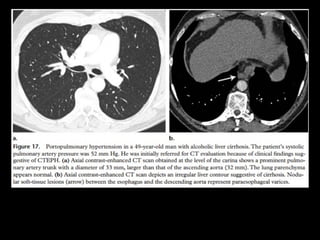

Hipertensão portopulmonar

Complicação da doença hepática crônica;

Prevalência de HAP em pacientes com cirrose é

baixa: 0,61% a 0,73%;

Associação com esquistossomose

Fisiopatologia:

Obstrução dos vasos pelos ovos, disfunção

endotelial, lesão de cisalhamento causada pelo

hiperfluxo sanguíneo e reações inflamatórias na

íntima.

Achados de imagem: Rx e TC

Aumento do calibre dos vasos pulmonares;

Afilamento dos vasos e oligoemia;

Sinais de cardiomegalia direita;

Esplenomegalia

Esquistossomose

http://radiographics.rsna.org/content/30/7/1753.full.pdf+html